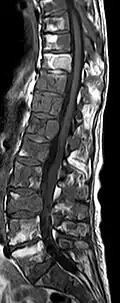

Avec l'IRM, on peut en particulier obtenir de bonnes images des tissus mous. C'est un processus idéal pour le diagnostic des métastases spinales (métastases des vertèbres). Avec l'IRM, on peut en outre rendre visible des complications supplémentaires dans la région des métastases spinales, comme des infections ou des blessures des tendons et ligaments, des œdèmes de la moelle osseuse après une fracture récente[120],[121], ou la compression de structures nerveuses[18]p. 16. Au moyen de séquences STIR, il est possible d'évaluer l'âge d'une fracture. Pour la détection des métastases, la pondération T1 avec des produits de contraste au gadolinium, comme l'acide gadotérique est particulièrement bien adaptée. Le produit de contraste s'accumule particulièrement fort dans les métastases[18],[122].

- Comparaison scanner/IRM pour des métastases ostéolytique d'un cancer du sein dans la colonne vertébrale

IRM natif avec pondération T1.

IRM sagittal natif avec pondération T1. On voit clairement l’extension jusqu'aux lames vertébrales.